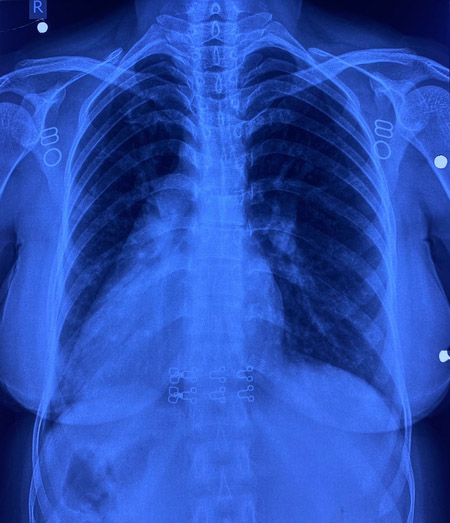

इस मरीज के सभी अंग सामान्य जगह के उलट यानी मिरर इमेज में थे। उसके दिल की जगह दाईं ओर थी, लिवर बाईं ओर, प्लीहा दाईं ओर और पेट भी दाईं ओर था। इसके साथ ही मरीज में जन्मजात आंशिक एट्रियोवेंट्रिकुलर कैनाल दोष जैसी जन्मजात हृदय रोग की समस्या भी थी।

सर्जरी के दौरान चिकित्सा टीम ने अत्यंत सावधानी बरतते हुए मरीज के हृदय दोष का सफल उपचार किया। मात्र 4 सेंटीमीटर के सूक्ष्म ‘इन्फ्रामैमरी’ चीरे के जरिए यह जटिल प्रक्रिया संपन्न की गई। ऑपरेशन के दौरान हृदय की कार्यप्रणाली को सुचारू रखने के लिए शरीर की बाहरी नसों की सहायता से ‘कार्डियोपल्मोनरी बाईपास मशीन’ का उपयोग किया गया। हृदय के दोष को ठीक करने के लिए मरीज की अपनी ‘पेरिकार्डियम’ (हृदय की सुरक्षा झिल्ली) से पैच तैयार किया गया और उसे बेहद बारीक टांकों के जरिए सटीक स्थान पर लगाया गया, ताकि हृदय के वाल्व और कंडक्शन सिस्टम को कोई क्षति न पहुंचे। सर्जरी के बाद मरीज की रिकवरी बहुत ही सहज रही और अब वह अस्पताल से जाने के लिए पूरी तरह फिट है। इकोकार्डियोग्राफी ने भी सफल सर्जरी की पुष्टि की।

साइटस इन्वर्सस अपने आप में बहुत ही दुर्लभ है और इसके साथ आंशिक एट्रियोवेंट्रिकुलर कैनाल दोष होना और भी कम होता है। आम तौर पर ऐसी सर्जरी में सीने की हड्डी काटनी पड़ती है, लेकिन इस केस में सिर्फ छोटे कॉस्मेटिक चीरे से सर्जरी की गई, जिससे यह दुनिया की पहली सर्जरी बन गई। मरीज रमबाई और उनके परिवार ने डॉ. नरेन्द्र सिंह झाझड़िया और पूरी टीम का दिल से धन्यवाद किया।